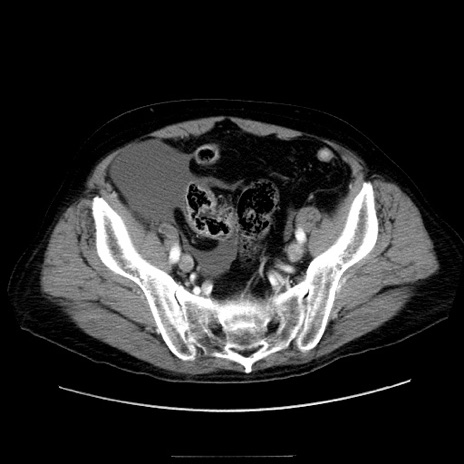

症例30(横断像)

【症例】80歳代男性

【現病歴】約6時間前から臍下部痛が出現。次第に腹部膨隆・背部痛も生じてきたため来院。背部痛の場所は変化しない。

【身体所見】意識清明、BT 36.3℃、BP  131/87mmHg、P 87bpm、SpO2 100%(RA)、臍周囲自発痛・圧痛あり、反跳痛なし、自発痛部位に一致して板状硬あり、腹部膨隆、腸雑音減弱、CVA tenderness両側陰性。